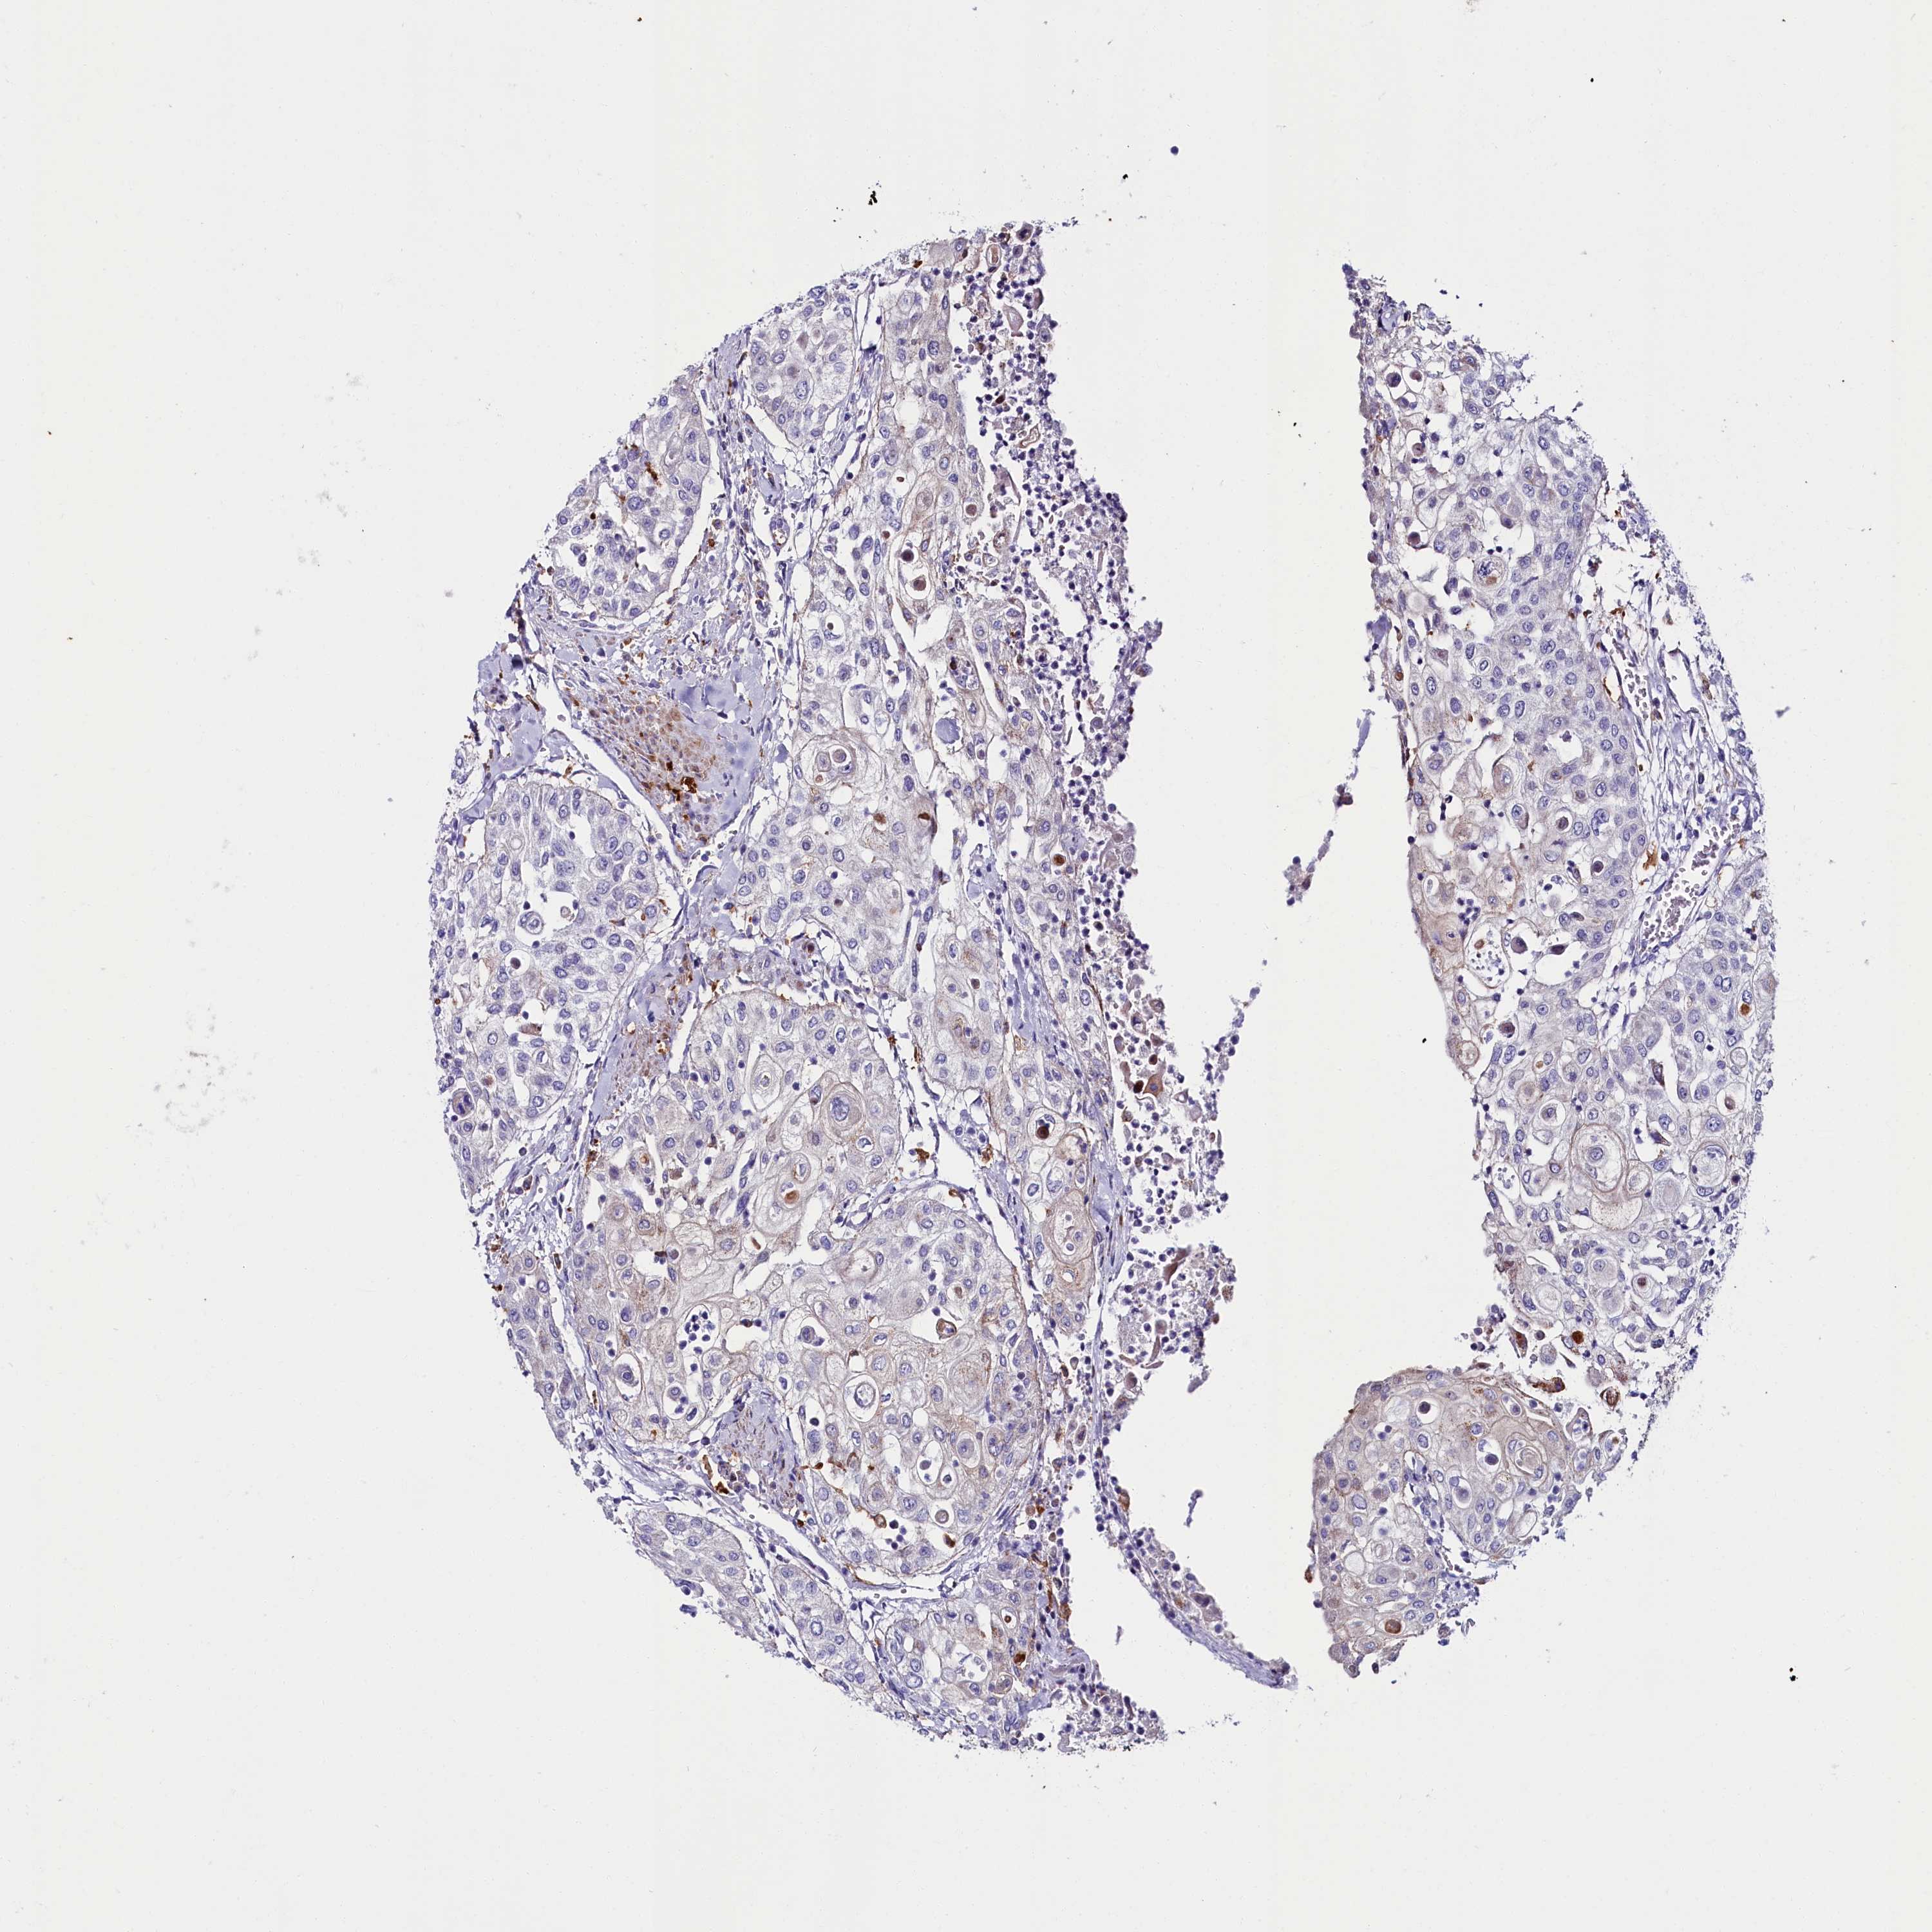

UROTHELIAL CANCER - Protein expressioni

A mouse-over function shows sample information and annotation data. Click on an image to view it in a full screen mode. Samples can be filtered based on level of antibody staining by selecting one or several of the following categories: high, medium, low and not detected. The assay and annotation is described here.

Note that samples used for immunohistochemistry by the Human Protein Atlas do not correspond to samples in the TCGA dataset.

Antibody stainingi

Antibody staining in the annotated cell types in the current human tissue is reported as not detected, low, medium, or high, based on conventional immunohistochemistry profiling in selected tissues. This score is based on the combination of the staining intensity and fraction of stained cells.

Each image is clickable and will lead to virtual microscopy that enables deeper exploration of all samples and also displays staining intensity scores, fraction scores and subcellular localization as well as patient and tissue information for each sample.

Antibody HPA042281

Antibody CAB024990

Urothelial carcinoma, High grade

Urothelial carcinoma, Low grade